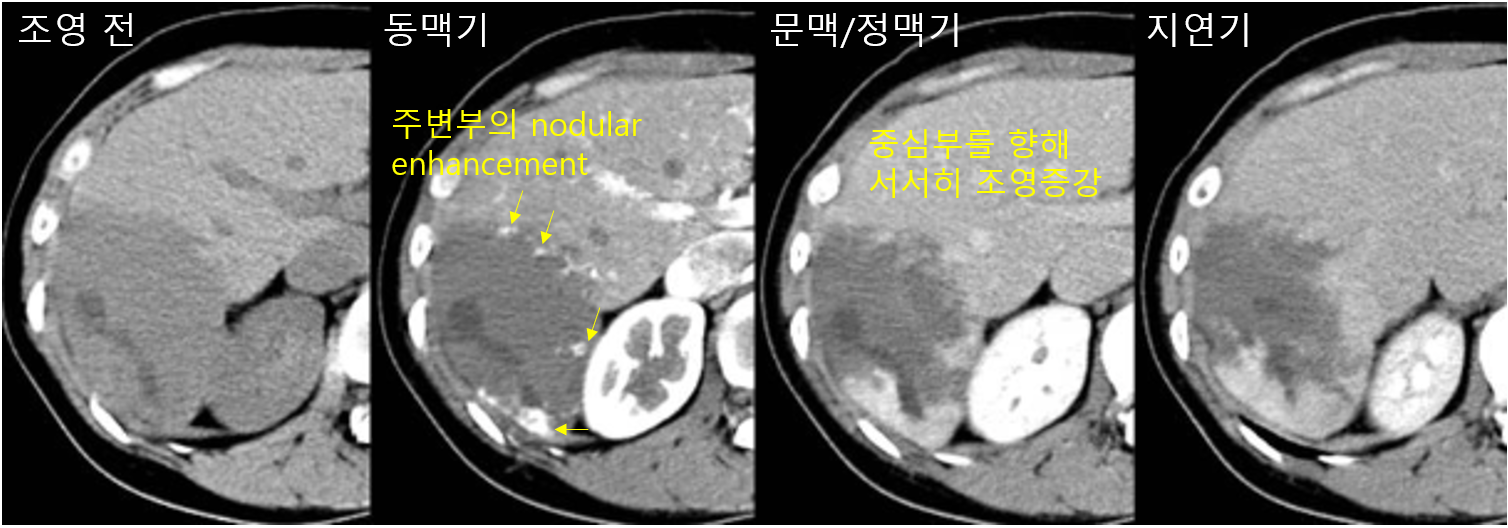

3) 검사소견: CT/MRI

(1) 동맥기: 주변부의 일부만 nodular하게 조영증강됨

(2) 문맥/정맥/지연기: 주변부→중심으로 서서히 조영증강됨